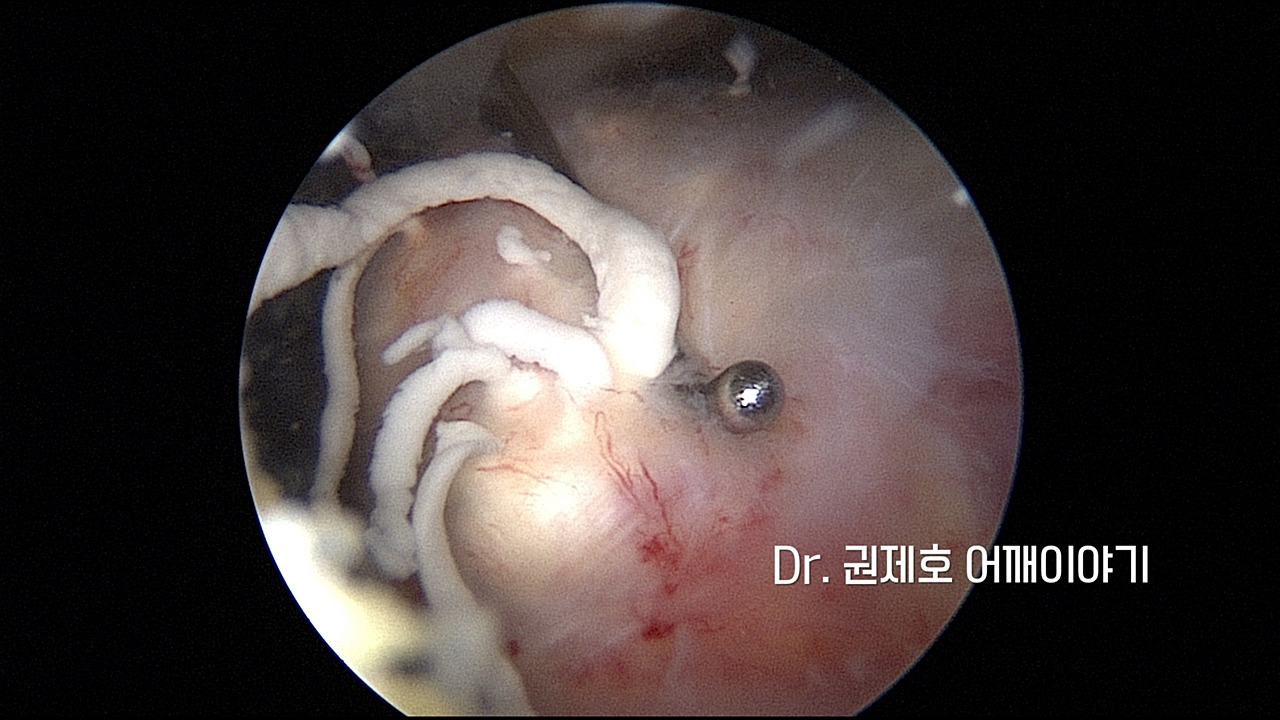

어깨에 생긴 석회성건염의 제거는 관절 내시경을 통해서 한다. 관절경 삽입구 2개를 만들어서 진행한다.

침착된 석회로 인해서 미세혈관즐이 울혈이 되어 있기에 찾기 쉽다. 흰색 덩어리가 인대를 싸고 있는 막안에 존재하는 석회 덩어리이다.